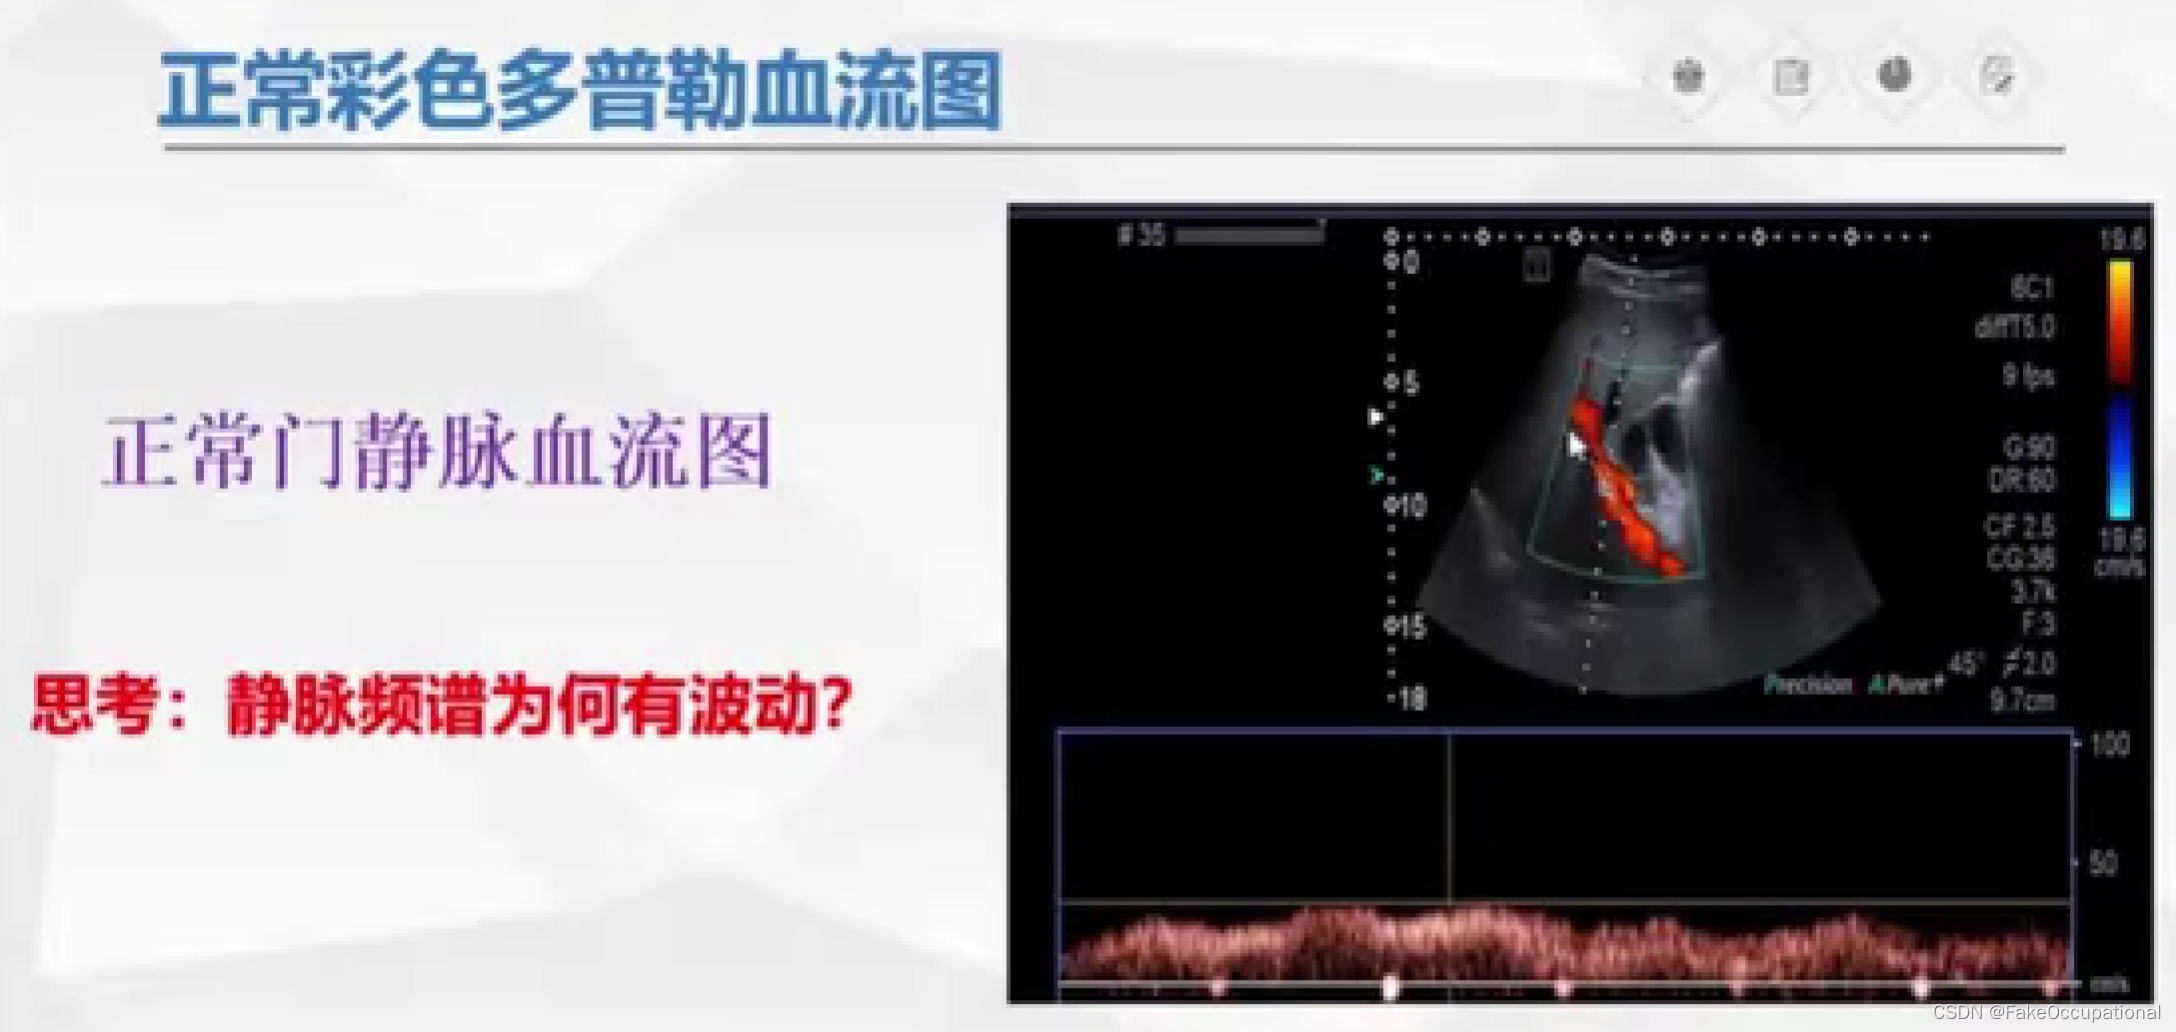

超声成像方法包括A型,B型,M型,D型(频谱多普勒,多普勒血流成像)。

D型超声

主要包括:

- 以频谱曲线显示,检测血流动力学参数:脉冲波多普勒(PW),连续波多普勒(CW),组织多普勒(TDI)

- 彩色编码实时显示血流方向、速度及血流性质:彩色多普勒血流成像(CDFI),彩色多普勒能量图(CDE)